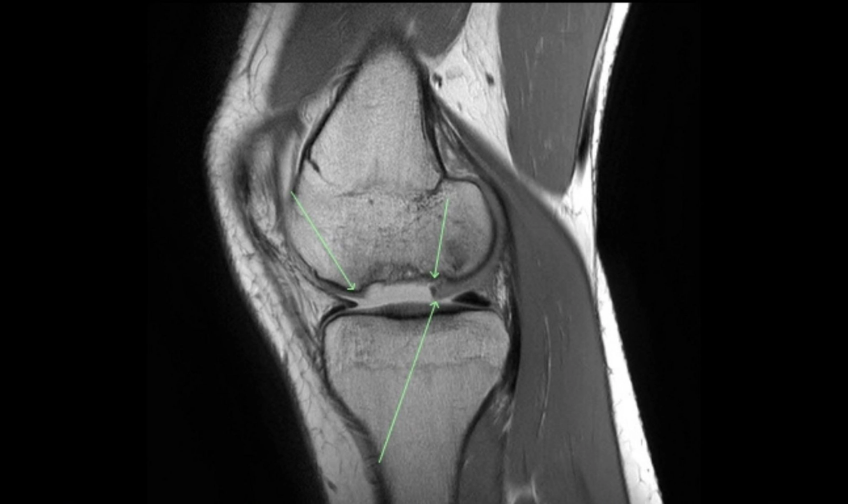

The Osteochondral Allograft Transplantion Surgery, commonly known as OATS, replaces damaged cartilage in the knee with healthy cartilage from a donor, relieving pain and restoring movement and function to the joint. A mosaicplasty is the name for a general procedure that treats severe cartilage damage, and the OATS procedure is a type of mosaicplasty.

Cartilage, or chondral, damage is known as a lesion and can range from a soft spot on the cartilage (Grade I lesion) or a small tear in the top layer to an extensive tear that extends all the way to the bone (Grade IV or “full-thickness” lesion). Sometimes a piece of cartilage breaks off and causes more damage to the cartilage and bone as it is ground in the joint.

While cartilage is essential for ensuring smooth, painless movement of the joints, some areas have a more critical need for the support and cushioning provided by the cartilage. During the OATS procedure, small plugs of healthy cartilage are taken from a donor and transferred to the area of damaged cartilage. In other forms of the procedure, cartilage may be removed from the patient’s own joints. However, allograft means that the cartilage comes from a donor individual instead.